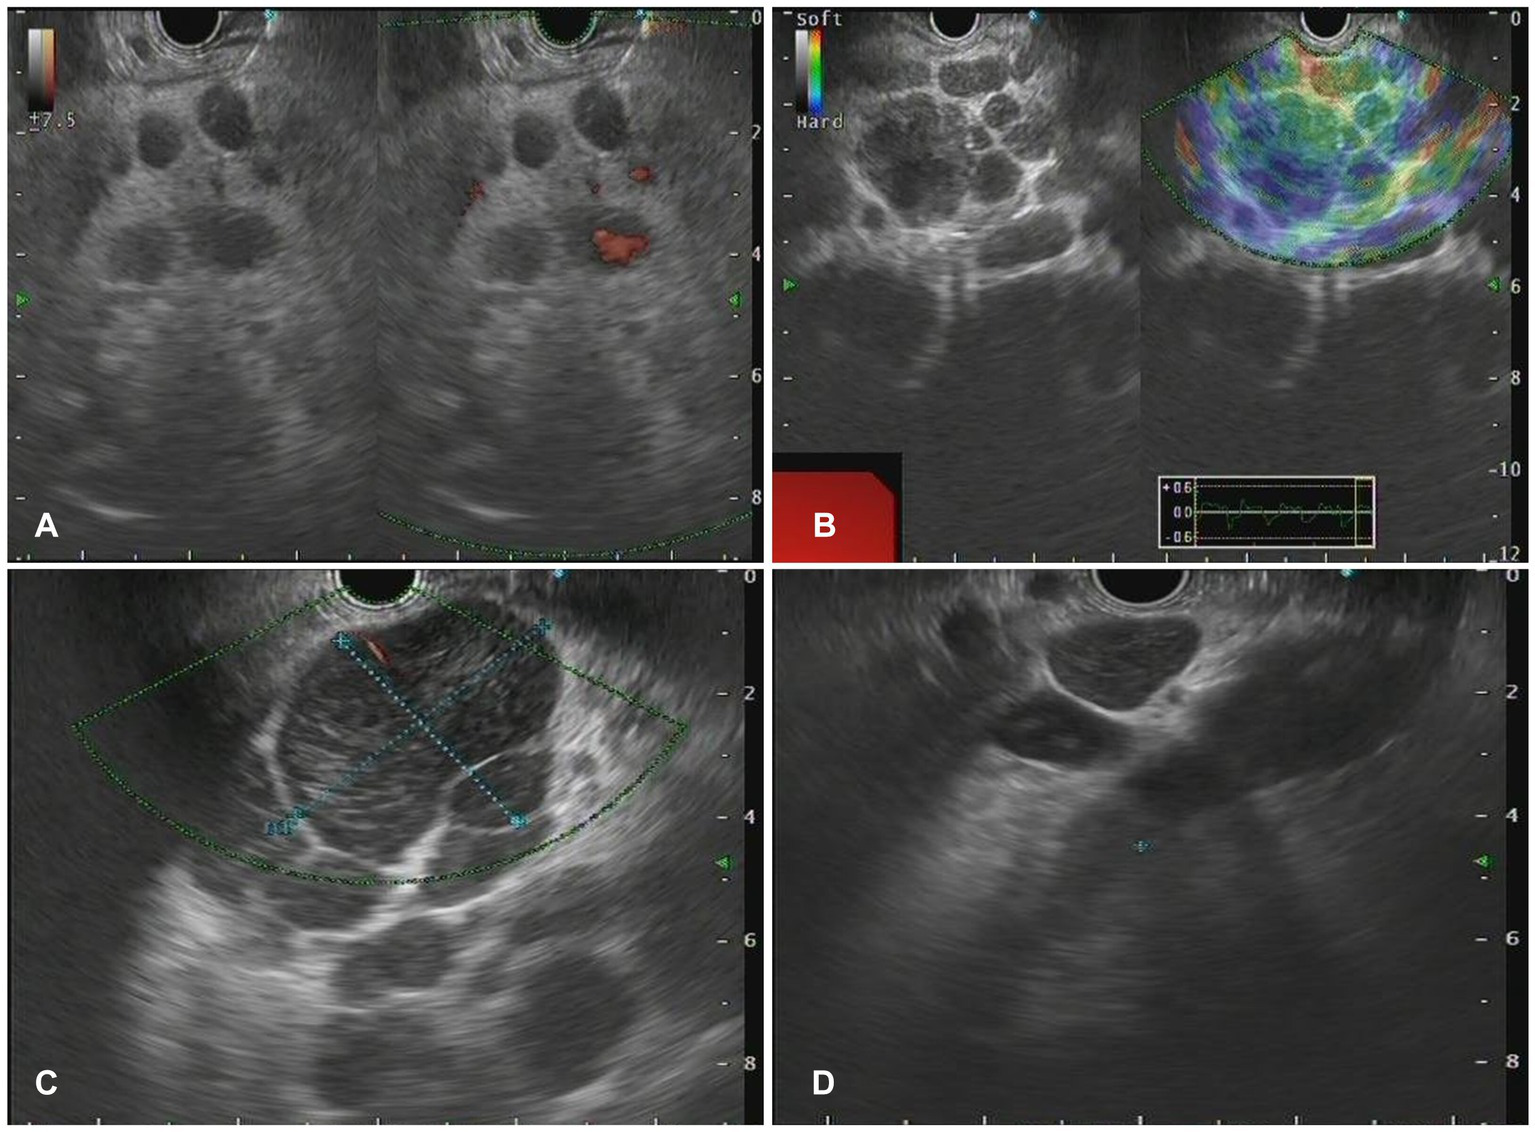

Figure 3

The Endoscopic ultrasonography image features for lymphoma. (A) A case of NKT cell lymphoma. EUS showed circular hypoechoic nodules with partial fusion, and no obvious blood flow signal was observed by Doppler. (B) In the case of follicular lymphoma, EUS showed multiple hypoechoic nodules and partial fusion. (C) One case of diffuse large B-cell lymphoma. EUS showed multiple hypoechoic nodules, Doppler showed a few blood flow signals, and elastic imaging suggested a hard texture. (D) A case of vascular immunoblastic T-cell lymphoma. EUS showed multiple circular hypoechoic nodules with partial fusion.